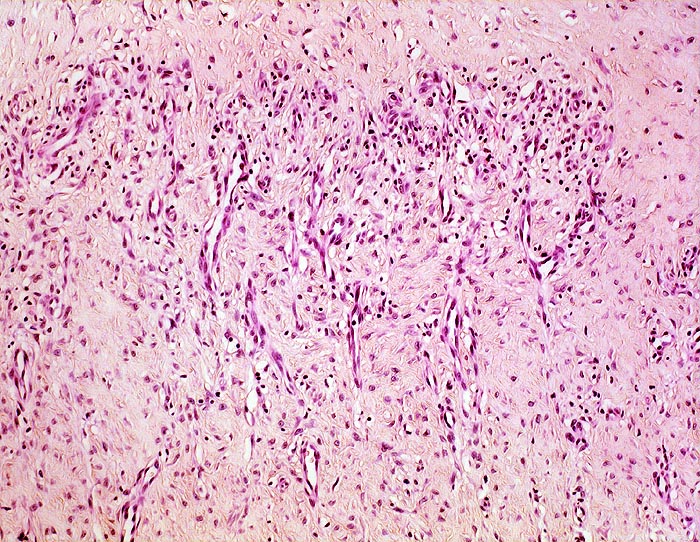

chronische Bursitis

Organisationsgewebe der Bursawand mit neugebildeten kapillären Gefässen zwischen fibroblastenreichem Bindegewebe. Lockere, vorwiegend perivaskuläre lymphohistiozytäre Infiltrate

Das Granulationsgewebe organisiert von innen her die nach mechanischer Belastung immer wieder von Neuem gebildeten Fibrinexsudate. Später wird das Granulationsgewebe ersetzt durch Narbengewebe.